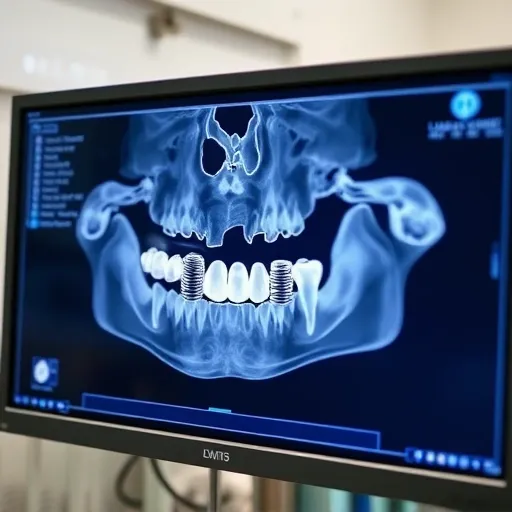

치과 진료의 오차를 줄이는 가장 중요한 요소는 장비입니다. 특히 3D-CT와 구강 스캐너 같은 디지털 장비의 도입 여부가 진단과 치료의 질을 결정합니다. 3D-CT는 육안으로 확인하기 어려운 신경관의 위치, 뼈의 밀도 등을 입체적으로 파악하게 합니다. 임플란트 식립 시 신경 손상 위험을 최소화하고 식립 위치를 정밀하게 계획하는 데 필수적입니다. 또한, 구강 스캐너는 인상재를 사용하여 본을 뜨는 기존 방식의 불편함을 해소합니다. 정확하고 빠르게 구강 구조를 스캔하여 보철물 제작의 오차율을 현저히 낮춥니다. 논산시 치과를 알아볼 때 해당 장비를 보유하고 있는지, 그리고 의료진이 해당 장비를 능숙하게 활용하여 치료 계획을 수립하는지 확인하는 과정이 필요합니다.

최근 임플란트 진료의 트렌드는 ‘네비게이션 임플란트’ 또는 ‘가이드 수술’입니다. 이는 3D-CT 촬영 데이터를 기반으로 컴퓨터 시뮬레이션을 통해 가장 이상적인 식립 경로를 미리 설정하고, 이를 바탕으로 제작된 맞춤형 가이드 틀을 사용하여 수술을 진행하는 방식입니다. 이 방식은 절개를 최소화하거나 무절개 수술을 가능하게 하여 출혈과 통증을 줄이고 회복 기간을 단축합니다. 논산시 치과 중 가이드 수술 시스템을 도입하고 자체적으로 가이드 제작 기술을 보유하거나 협력 체계를 갖춘 곳은 높은 수준의 정밀 진료가 가능함을 의미합니다.

치과 장비가 치료 결과를 좌우한다: 3D-CT와 구강 스캐너의 역할

디지털 치과의 핵심은 진단 장비입니다. 논산 지역 치과들이 경쟁적으로 도입하고 있는 3D-CT와 구강 스캐너는 단순한 첨단 장비를 넘어, 환자 안전과 치료 정밀도를 획기적으로 향상시키는 도구입니다. 이 두 장비의 역할과 환자에게 미치는 이점을 구체적으로 살펴보겠습니다.

1. 3D-CT (Cone-Beam CT)를 통한 입체적 진단

기존의 2차원 파노라마 엑스레이는 턱뼈의 높이와 치아의 전반적인 배열만을 파악할 수 있었습니다. 반면, 3D-CT는 치조골의 폭, 신경관의 주행 경로, 부비동(코 옆의 공간)의 위치 등을 3차원으로 구현합니다. 이는 임플란트 식립 시 뼈의 두께가 부족한 경우, 사전에 골 이식을 계획하거나 식립 각도를 미세하게 조절하는 데 필수적입니다. 특히 논산 지역에서 고령 환자의 임플란트 수요가 높다는 점을 고려하면, 뼈의 상태가 좋지 않은 환자에게 3D-CT는 안전한 수술을 위한 기본 전제 조건이라고 할 수 있습니다.

- 정확한 신경관 위치 파악: 하악 임플란트 시술 중 발생할 수 있는 신경 손상 위험 최소화.

- 골 이식 필요성 예측: 뼈의 밀도와 양을 정확히 측정하여 불필요한 수술 방지.

- 사랑니 발치 난이도 확인: 매복 사랑니의 깊이와 신경관 근접도를 미리 파악하여 안전한 발치 계획 수립.